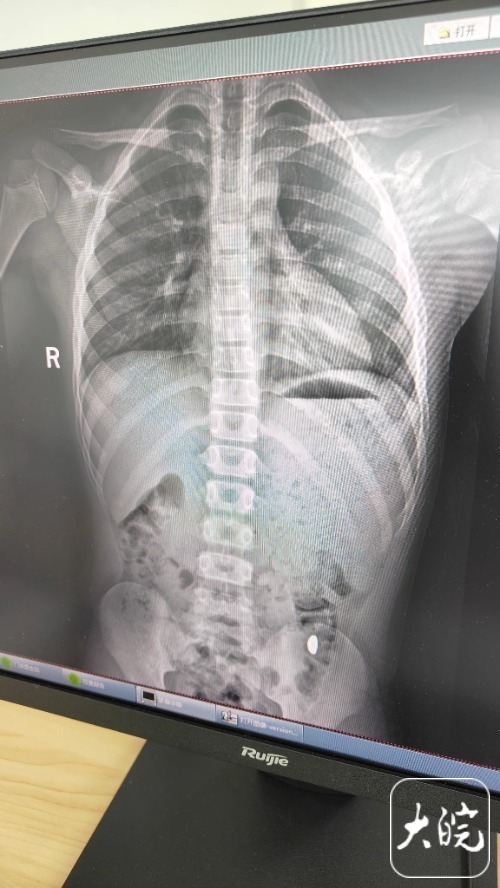

昆山市第五人民医院门诊病历单显示,医生在现病史一栏写着,患儿5天前误吞约10克黄金,期间解2次大便未发现,目前无腹痛、呕吐等症状,诊断结果显示胃内有异物。